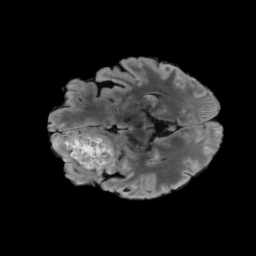

To see when and how X-Diffusion fails, we conducted an experiment on healthy brains (no tumour) using IXI dataset, by running an X-diffusion trained on BRATS brain tumor dataset. Our X-Diffusion achieved a PSNR of 35.86 dB on the IXI dataset despite being trained on the BRATS dataset. We then ran the tumour segmenter on the set of 582 healthy scans and corresponding generated MRIs. The segmenter predicted tumours in 9.9% of the real healthy brains and in 11.3% of the generated brain MRIs. Some of these tumor hallucination examples fron X-Diffusion generation are shown in Figure 10.

| Hallucination | Reference | Hallucination | Reference | Failure | Reference |

This shows how the generated MRIs indeed preserve the tumour information and can act as an affordable and informative pseudo-MRI, before conducting an actual costly MRI examination in hospitals. Given that our model has been trained on brain scans all with tumours, we expect to see hallucinations of tumours in healthy scans. We report two cases of failure of our model in Figure VII. Hallucinations of tumours on healthy samples represent 2% of the test set.